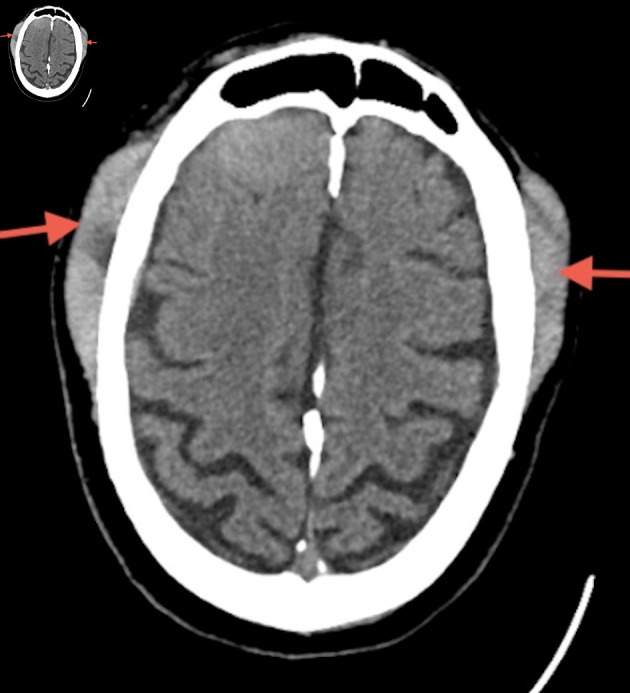

外周T细胞淋巴瘤(PTCL-NOS)是一种罕见的侵袭性非霍奇金淋巴瘤(NHL)亚型,起源于成熟的T细胞或自然杀伤细胞(NK),约占所有NHL病例的5%。虽然PTCL-NOS通常累及淋巴结,但结外部位如皮肤、胃肠道、肝脏和肺部也可能受到影响。中枢神经系统(CNS)受累是极其罕见的,特别是在最初的表现。当它确实发生时,最常受影响的是大脑,其次是脊髓和脑膜。我们报告一例罕见的PTCL-NOS合并继发性中枢神经系统淋巴瘤累及脑膜的病例。我们的病人是一名75岁的男性,患有多种合并症,表现为几周的间歇性头痛。影像学显示多发性轴外脑病变,浸润到颅外软组织、硬膜外间隙、脑膜和脑实质。随后的淋巴结活检证实PTCL-NOS。他开始使用利妥昔单抗、环磷酰胺、阿霉素、长春新碱和强的松(R-CHOP),并计划使用大剂量甲氨蝶呤。此后,患者因各种并发症多次再次入院,并在诊断后约2.5个月死亡。我们得出结论,PTCL-NOS继发性中枢神经系统受累非常罕见,预后较差,中枢神经系统诊断后的中位生存期约为1.1个月。早期诊断和量身定制的治疗策略,包括中枢神经系统穿透剂,是必不可少的。需要继续研究以更好地了解和改善这种侵袭性疾病的结果。

Peripheral T-cell lymphoma, not otherwise specified (PTCL-NOS), is a rare and aggressive subtype of non-Hodgkin lymphoma (NHL) that arises from mature T or natural killer (NK) cells, accounting for about 5% of all NHL cases. While PTCL-NOS typically involves lymph nodes, extranodal sites such as the skin, gastrointestinal tract, liver, and lungs can also be affected. Central nervous system (CNS) involvement is extremely rare, especially at the time of initial presentation. When it does occur, the brain is most commonly affected, followed by the spinal cord and meninges. We present a rare case of PTCL-NOS with secondary CNS lymphoma involving the meninges at initial diagnosis. Our patient is a 75-year-old male with multiple comorbidities who presented with several weeks of intermittent headaches. Imaging showed multiple extra-axial brain lesions with infiltration into extracranial soft tissues, epidural space, meninges, and brain parenchyma. A subsequent lymph node biopsy confirmed PTCL-NOS. He was started on rituximab, cyclophosphamide, doxorubicin, vincristine, and prednisone (R-CHOP), with plans for high-dose methotrexate. Thereafter, the patient was readmitted several times due to various complications and expired approximately 2.5 months after diagnosis. We conclude that secondary CNS involvement in PTCL-NOS is very rare and has a poor prognosis, with a median survival after CNS diagnosis of about 1.1 months. Early diagnosis and tailored treatment strategies, including CNS-penetrating agents, are essential. Continued research is needed to better understand and improve outcomes for this aggressive disease.